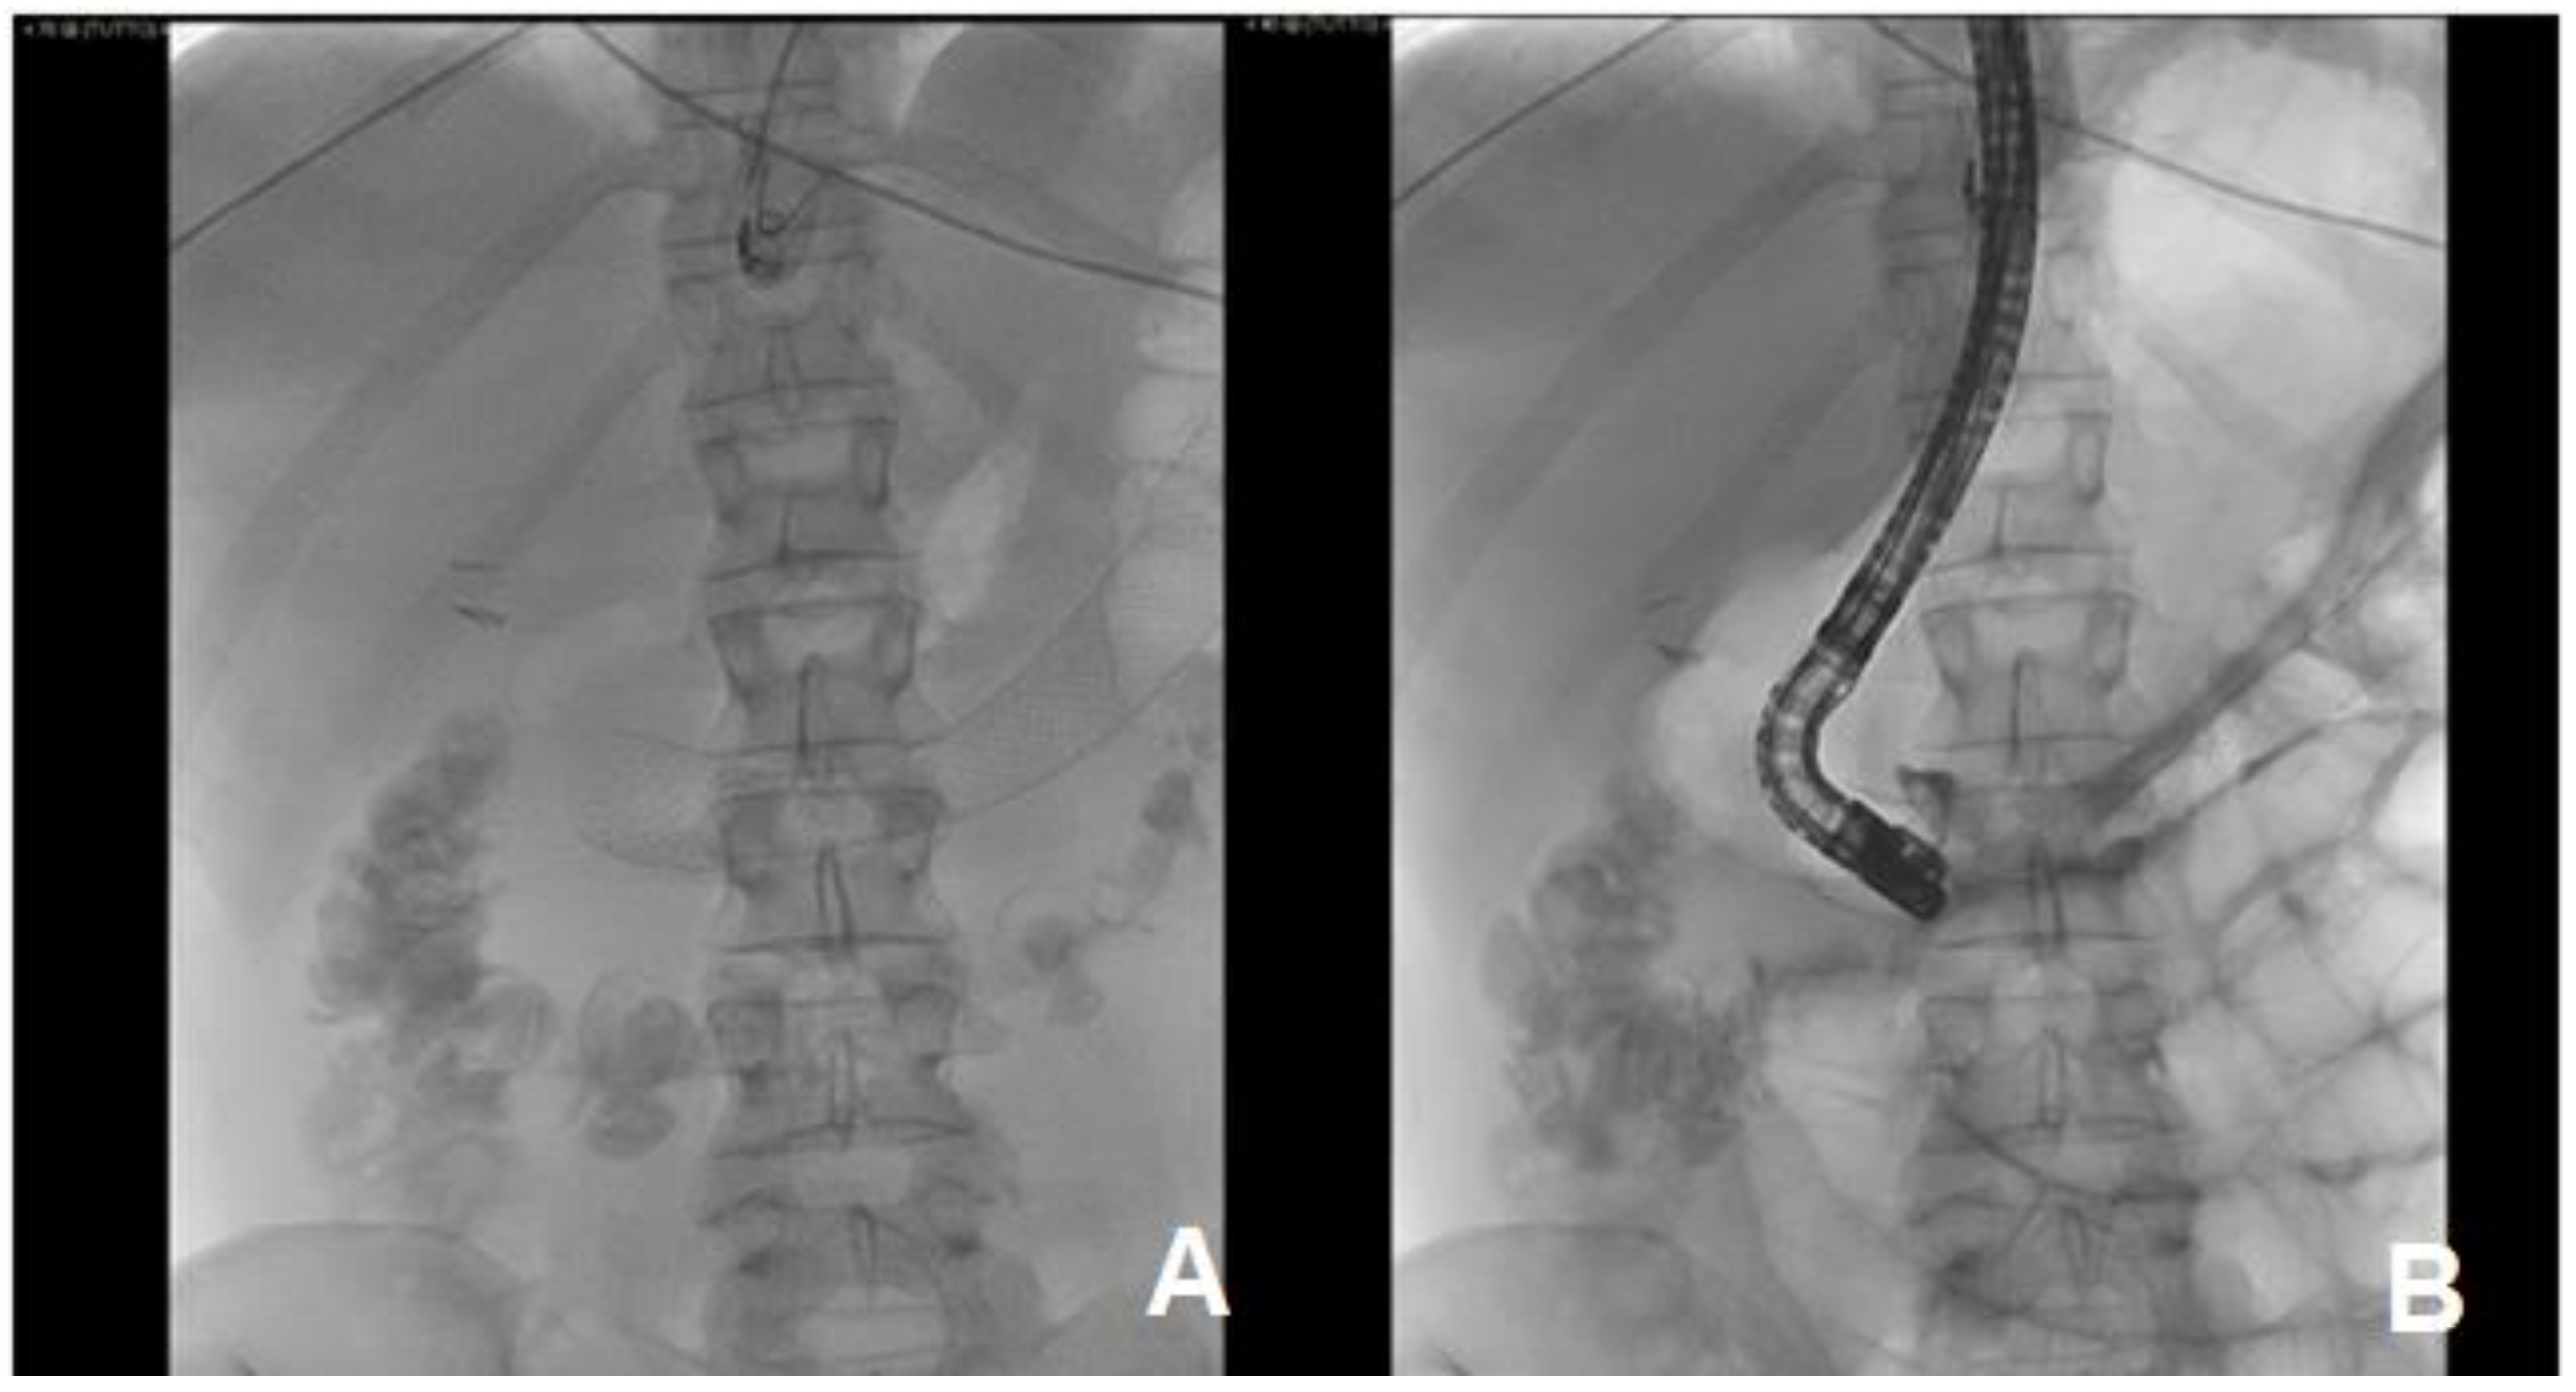

2. Case Discussion